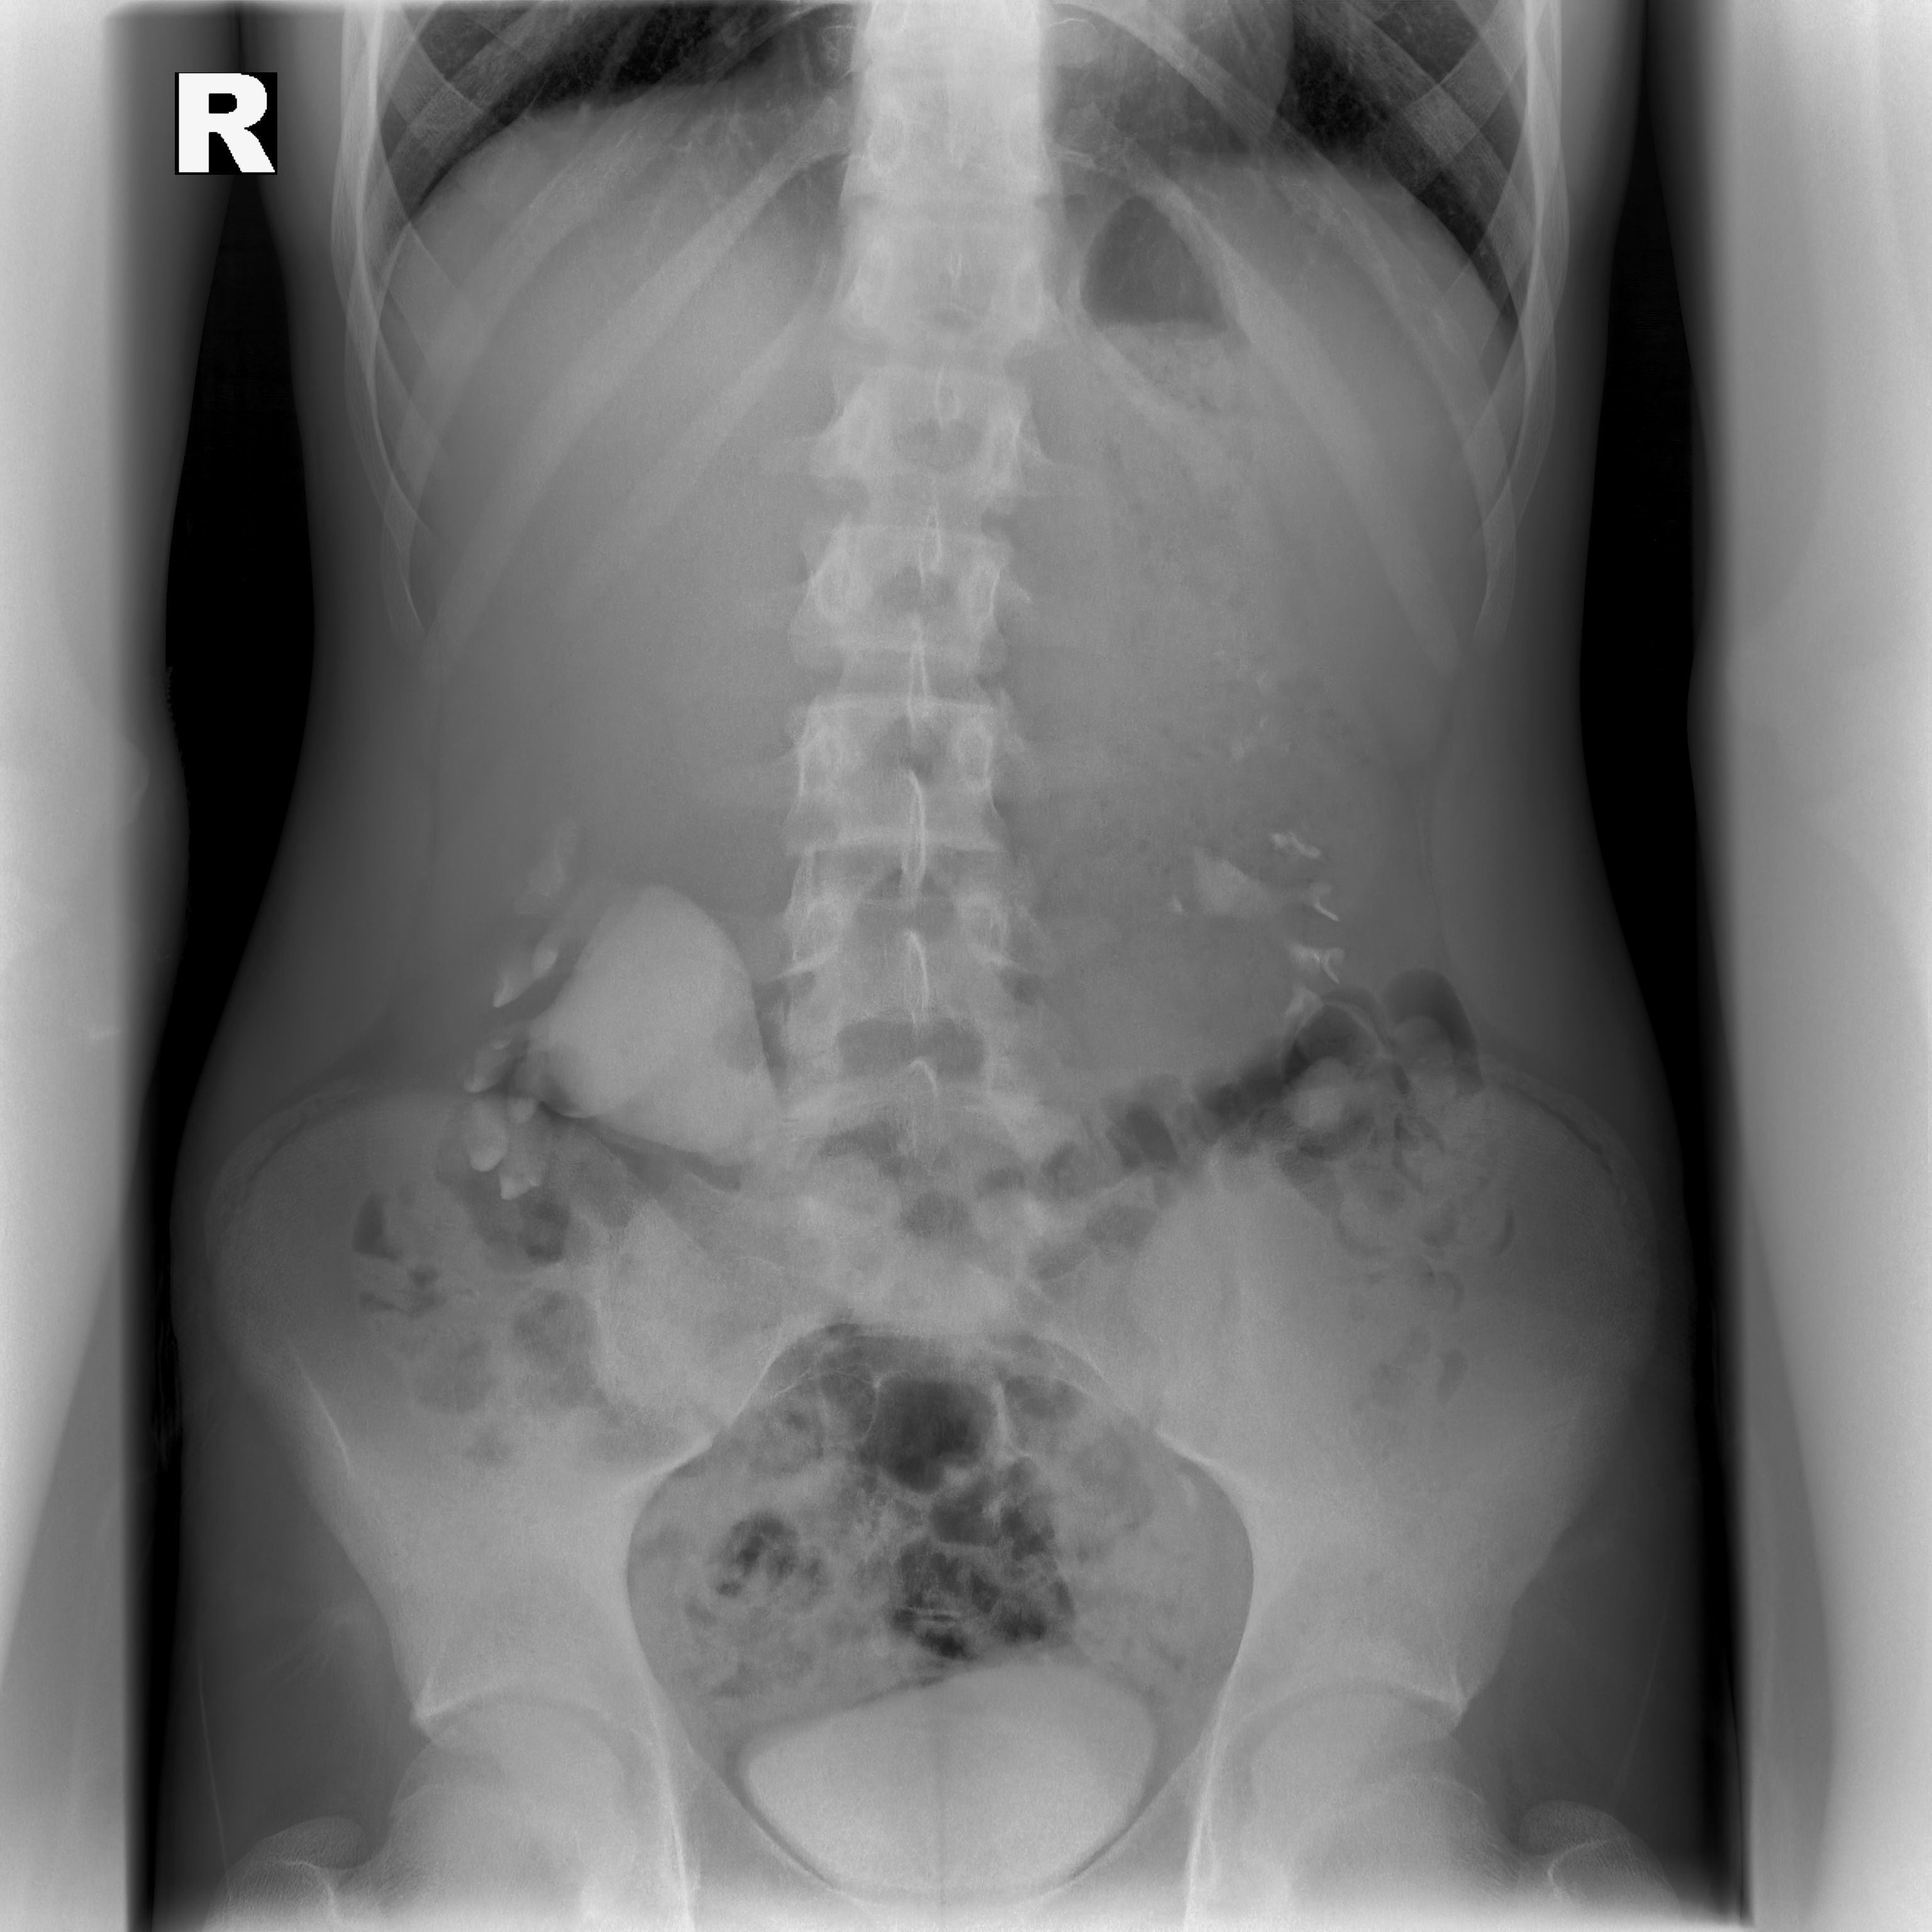

В урологическое отделение экстренно госпитализирован подросток с жалобами на острую боль в животе. В ходе обследования врачи детской окружной больницы Нижневартовска выявили у подростка нефроптоз высокой степени, осложненный гидронефрозом – почка из своего физиологического местоположения опускалась в малый таз, вызывая выраженный болевой синдром и ухудшая отток мочи. «Нефроптоз у подростков – частое явление. Низкие степени, как правило, лечатся путем назначения общих рекомендаций, направленных на укрепление передней брюшной стенки: плавание, укрепление пресса, корректировка питания с целью увеличения подкожно жировой клетчатки, чтобы жировая капсула фиксировала почку. Так как у нашего пациента из-за заболевания началось осложнение – гидронефроз, мы выбрали более активную тактику – хирургическое лечение, направленное на фиксацию почки в необходимом положении», - рассказал Николай Обухов, заведующий детским уроандрологическим отделением Нижневартовской окружной клинической детской больницы.

Заведующий уроандрологическим отделением Николай Обухов и врач-уролог Руслан Муллагалиев установили сетчатый имплант, в который поместили почку, и зафиксировали его к поясничной мышце. Пациент провел несколько дней в отделении и был выписан на амбулаторное наблюдение с положительной динамикой – отсутствием болевого синдрома и расстройством мочеиспускания. «Операция прошла без осложнений, длилась не больше часа. Ребенок, миновав реанимацию, находился под наблюдением урологов. Спустя два месяца после проведения операции ребенок был госпитализирован к нам в отделение для проведения контрольного обследования. У нашего пациента нефроптоз не выявлен», - рассказал Николай Обухов.